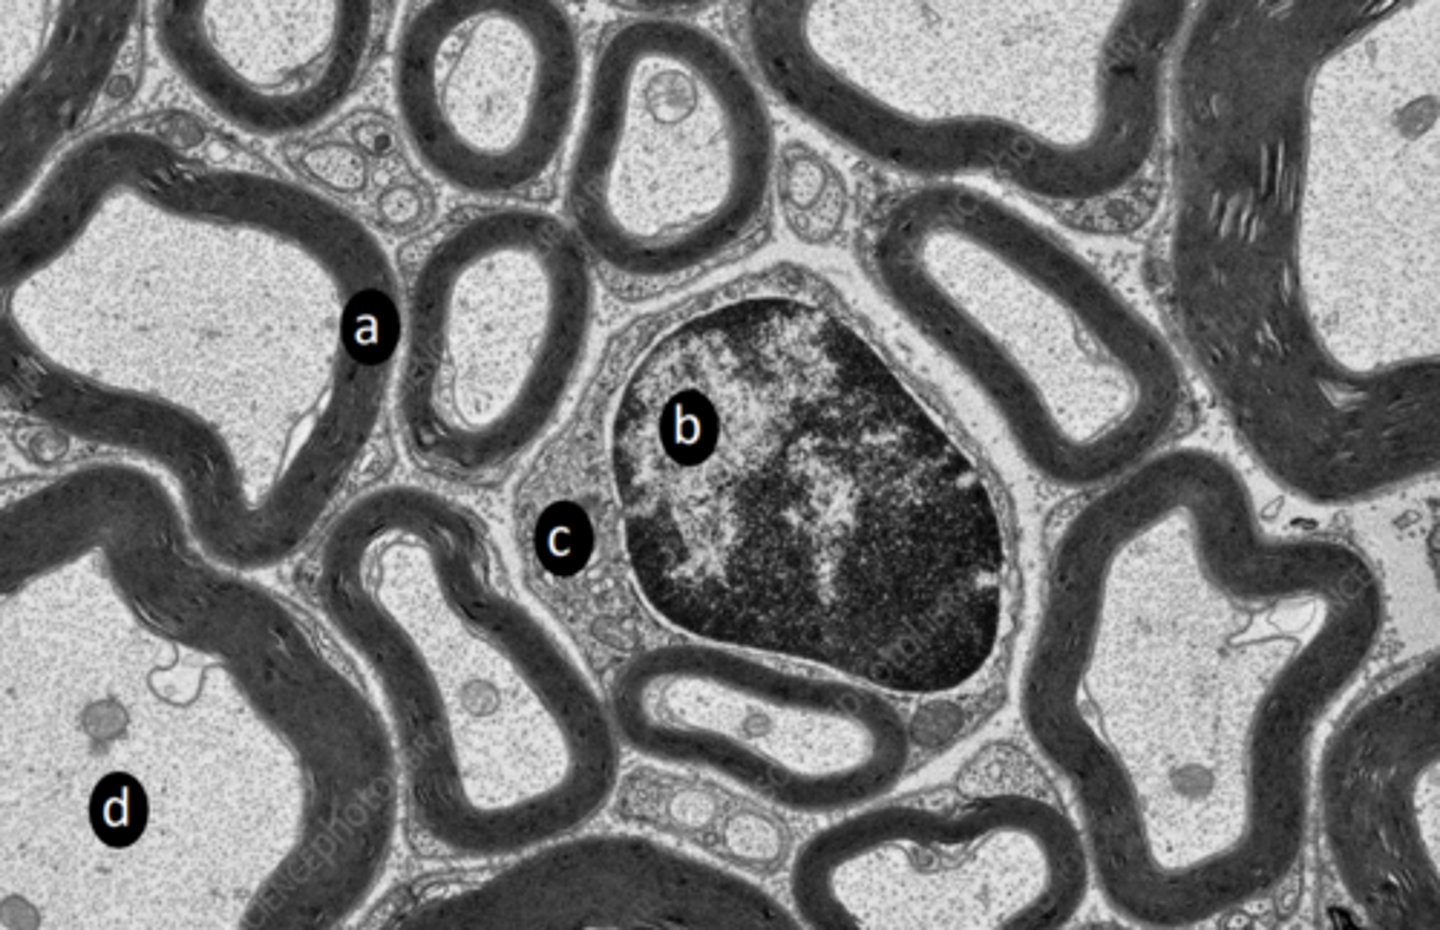

extrafusal myofibers

a: specific tissue type

intrafusal muscle fiber

b: specific tissue type

intrafusal muscle fiber (muscle spindle)

c: specific tissue type

stretch receptor, proprioception: detect length and velocity

function of c?

vein

e: structure

nerve fibers

f: structure

CT

g: tissue type